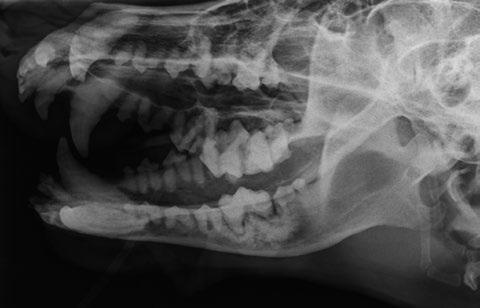

Diagnóstico y estadificación

Son tumores que pueden pasar desapercibidos y ser un hallazgo en la exploración odontológica de rutina. Por ello, si localizamos este tipo de crecimientos

Según un estudio donde se analizaron 68 perros afectados por tumores orales de posible origen odontogénico en un hospital docente veterinario entre los años 1995 y 2005, la distribución de este tipo de tumor en la cabeza fue la siguiente (figura 1A):

• 24 % maxila rostral

• 6 % maxila caudal

• 41 % mandíbula rostral

• 29 % mandíbula caudal

debemos hacer un buen diagnóstico y estadificación, ya que se trata de un tumor muy agresivo a nivel local que requiere un diagnóstico rápido y preciso y una extirpación quirúrgica adecuada a pesar de ser descrito como benigno. En el proceso diagnóstico del AAC se debe realizar un examen completo del paciente, estudio radiológico y, en aquellos casos que sea posible, el estudio complementario con TC para obtener más información acerca de su extensión (figura 1B). A nivel radiológico se observa una masa infiltrativa asociada al diente que causa desplazamiento dental y osteólisis variable, y que puede presentar mayor o menor apariencia quística (figura 2).

La principal diferencia del AAC con otros tumores odontogénicos es su capacidad de invadir hueso esponjoso, por lo que en radiología se observa infiltración ósea grave, desplazamiento dental e incluso reabsorción dental tanto a nivel local como a distancia. El mayor inconveniente de la evaluación radiográfica de estos tumores es la infravaloración de la extensión del hueso afectado, por lo que es conveniente realizar una tomografía computarizada para determinarla con mayor exactitud (Tjepkema, 2020).

La principal diferencia del AAC con otros tumores odontogénicos es su capacidad de invadir hueso esponjoso, por lo que en radiología se observa infiltración ósea grave, desplazamiento dental e incluso reabsorción dental tanto a nivel local como a distancia.